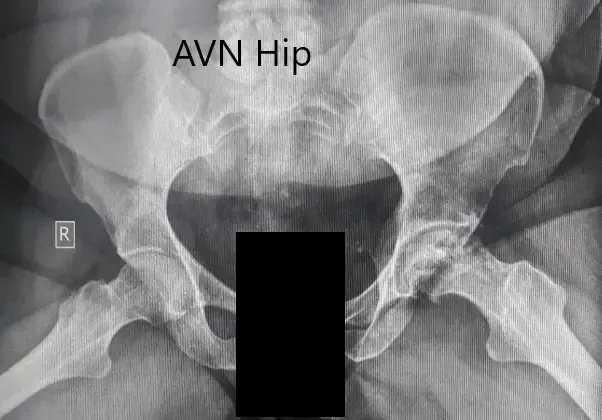

Se obtuvo una radiografía que sugería una pérdida severa de espacio articular con cambios en acetábulo en la cadera izquierda. Se perdió el contorno esférico de la cadera izquierda. Esclerosis y quistes subcondrales estaban presentes en la cadera izquierda con colapso.

Radiografía preoperatoria de la pelvis con ambas caderas en la vista lateral de patas de rana que muestra cambios en el AVN en la cadera izquierda.